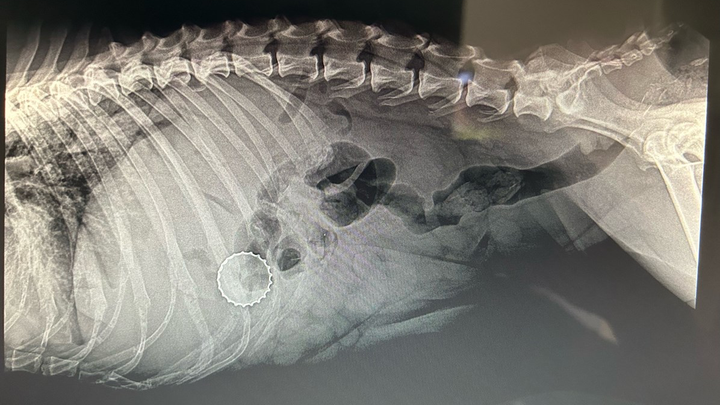

Chosen was found as a stray about a month ago and has been safe while waiting for her spay appointment. Today, during that visit, veterinarians discovered something shocking. Chosen has a bottlecap lodged inside her body.

This is a life threatening condition that requires immediate surgery. Her spay could not be performed because removing the bottlecap is now urgent. Without surgery, Chosen is at serious risk of infection, internal damage, and worse.